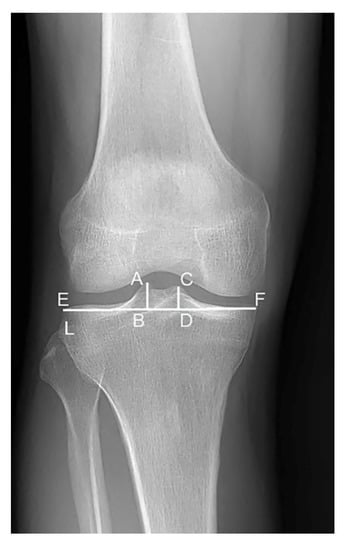

2.2. Radiograph Technique

2.3. Measurements